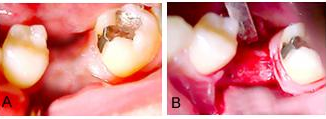

O dente 36 foi extraído com Regeneração Tecidual Guiada. Tinha problemas periodontais com bolsa periodontal profunda, envolvimento de bifurcação, grande perda óssea. Várias tentativas de tratamento periodontal foram realizadas ao longo de mais de 7 anos. Quando foi detectada uma cárie na área da bifurcação, separando a raiz mesial da distal e um agravamento da perda óssea na região, o dente foi condenado.

Com este prognóstico sombrio, o plano de tratamento indicado foi a extração do dente seguido de ROG, Regeneração Tecidual Guiada.

Figuras 1 a, b e c.

Figura 1a, mostra a sonda milimetrada penetrando mais de 10mm dentro da lesão na área da bifurcação.

Figura 1b, o retalho total foi realizado e rebatido, com a cureta MacCall 13-14, todo tecido de granulação foi removido, durante esse procedimento a coroa se soltou e foi removida da raiz.

Figura 1c, mostra o momento que a coroa foi removida e parte da raiz mesial, fraturada saiu junto com o núcleo, expondo todo defeito ósseo na área da bifurcação.